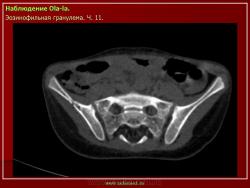

Из опубликованных наблюдений н сайте.